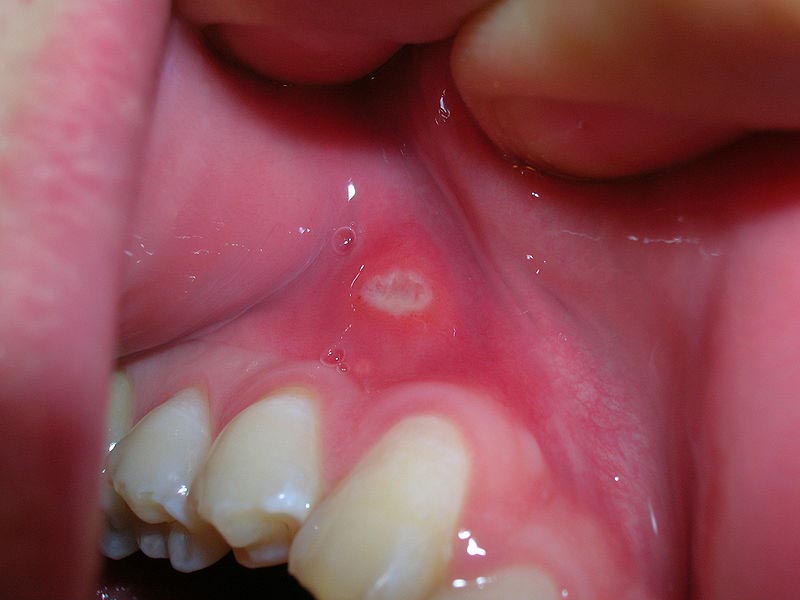

Afte, koje su medicinski poznate kao aftozni ulkusi, predstavljaju male, plitke rane koje se često pojavljuju na sluznici usne šupljine. Ove rane, iako nisu opasne, mogu izazvati značajnu nelagodu i bol, otežavajući svakodnevne aktivnosti poput jedenja, pijenja i govora. Aftozni ulkusi obično započinju kao bijele ili žućkaste ranice koje su okružene crvenim rubom. Dok većina afti ostaje mala, neke mogu narasti do 2,5 cm u promjeru, a najčešće se pojavljuju na jeziku, desnima, nepcu, unutarnjoj strani usana i ispod jezika. Ove rane mogu biti uzrokovane različitim faktorima, a njihova pojava može se manifestirati u različitim oblicima.

Simptomi afti obuhvataju pojavu jedne ili više bolnih ranica u ustima, osjećaj peckanja ili žarenja, te male okrugle ranice bijele, sive ili žute boje s crvenim rubom. U težim slučajevima, osobe mogu doživjeti povišenu temperaturu, iscrpljenost, te otečene limfne čvorove. Uzroci pojave afti još uvijek nisu potpuno razjašnjeni, ali postoji niz faktora koji mogu potaknuti njihov nastanak. Na primjer, stres je jedan od najčešćih uzroka, jer može oslabiti imunološki sistem i povećati osjetljivost na upale. Također, ozljede sluznice (npr. ugrizi ili gruba hrana) mogu izazvati afte. Konzumacija kisele hrane poput agruma ili začinjene hrane takođe može doprinositi razvoju aftoznih ulkusa. Osobe koje imaju nutritivne nedostatke, posebno nedostatak vitamina B12, folne kiseline, željeza ili cinka, takođe su podložnije razvoju afti. Upotreba određenih lijekova, kao što su nesteroidni antiinflamatorni lijekovi, može dodatno pogoršati situaciju.